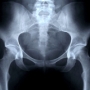

A röntgen a csípő- és medencetörések közel harmadát nem képes kimutatni – állítják kutatók, egyúttal pedig arra figyelmeztetnek, hogy rossz diagnózishoz és műhiba-perekhez vezethet, ha az ilyen esetekben csak a röntgenfelvételeket veszik figyelembe.